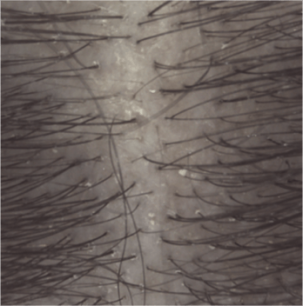

Résultats d'efficacité

Prurit dès les 1ères applications (2)

Induration à 1 mois (3)

(1) Etude clinique auprès de 54 sujets présentant un psoriasis du cuir chevelu léger à modéré. Phase d’attaque de 4 semaines : 3 shampoings par semaine.

(2) Évaluation par le sujet de l’intensité du prurit à J8.

(3) Évaluation clinique de l’induration des plaques à J29.